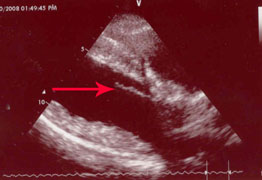

The picture below left is Chase's mitral valve from 2008, when he was three years old. You can see the red arrows that point to the leaflets that form the flap mentioned above. Compare that to the image on the right, which is Chase's uncle Indy, at 7 years old. The leaflet is very smooth and regular.

Indy's Mitral Valve at 7 years |